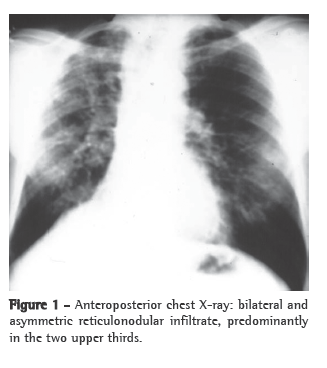

A simple chest X-ray (Figure 1) can reveal asymmetric reticulonodular infiltrate, predominantly in the two upper thirds of both lungs, accompanied by hypertransparent areas at the lung bases.(1,2,4)

The chronic unifocal/multifocal form is the most common form of paracoccidioidomycosis, accounting for 90% of the cases; males are predominantly affected. The unifocal form is characterized by a chronic progression, predominantly accompanied by weakness, weight loss, cough, dyspnea, reticulonodular infiltrate (generally in the two upper thirds of the lungs) and distal hypertransparent areas at both lung bases.

The multifocal form is characterized by the involvement of extrapulmonary sites, such as the skin, the oral mucosa (mulberry-like stomatitis), the pharyngeal mucosa or the laryngeal mucosa (or a combination of the two) and the apices of teeth. The symptoms of the multifocal form include pain during mastication, sialorrhea and odynophagia. Wasting is common due to a delay in seeking medical assistance. A chest X-ray reveals the same lesions as those observed in the unifocal form.